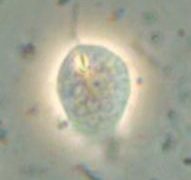

ヒストモナス:ヒストモナス・メレアグリディス(Histomonas meleagridis)、鞭毛虫類のトリコモナス類に属します。虫体は形態によって内腔型と組織型とに分けられます。内腔型は感染初期に盲腸腔内にみられ、おおきさは5~30㎛、形...